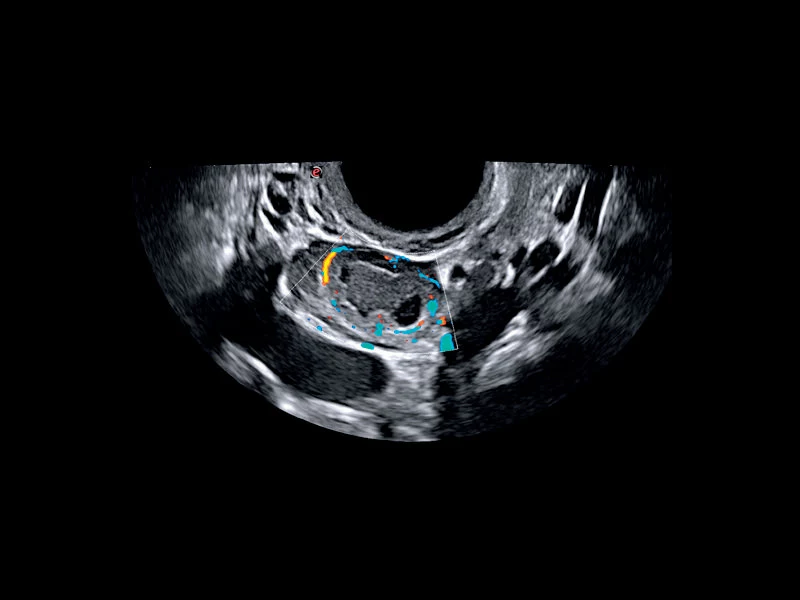

MyLab™C25 - Mioma PD

MyLab™C25 - Mioma PD